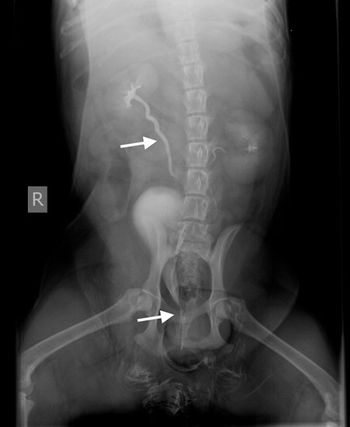

Abdominal radiographs are a rapid, readily available method to give an overview of the abdomen. Though most people believe ultrasound is the new modality of choice for abdominal evaluation, the limitations of ultrasound not being able to penetrate gas as well as the technical ability and time to acquire images still make abdominal radiographs a great first modality in the patient with acute abdominal pain.

The use of radiography to examine the abdomen is full of complications. Radiographs are very good at determining the difference between bone and gas, but soft tissue and fluid are the same opacity. When dealing with intra-abdominal lesions, the main goal is to differentiate one soft tissue mass from a normal soft tissue structure from abdominal fluid. Ultrasound uses high frequency sound waves to accomplish what radiographs cannot.